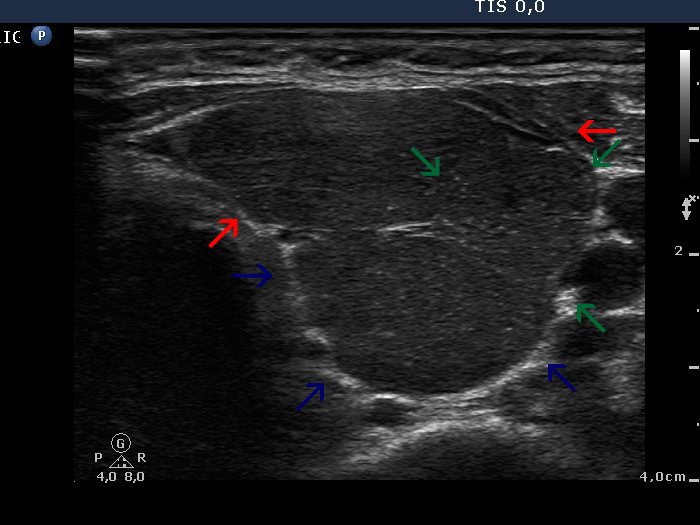

Graves' disease - Case 1289 (ultrasonographic picture 4b)

Left lobe, transverse scan. This image demonstrates the substructure of a thyroid lobe. The three pseudolobules are marked with different arrows.